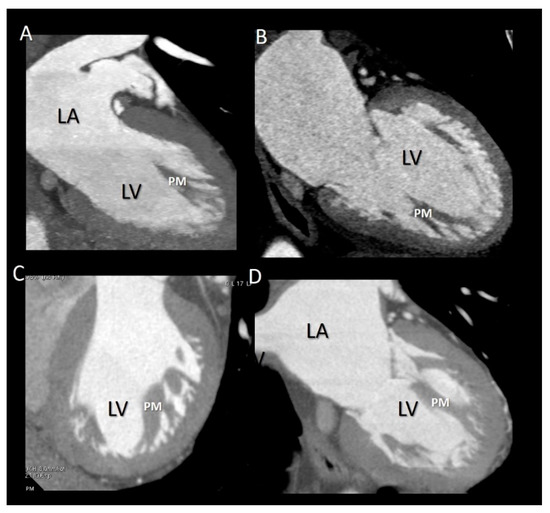

Figure 8.

(A,B) 2D TTE and (C,D) CMR cross-sections in diastole (A,C) and in systole (B,D) showing the longitudinal contraction of papillary muscle (PM) preventing leaflet eversion during the systole (see text).